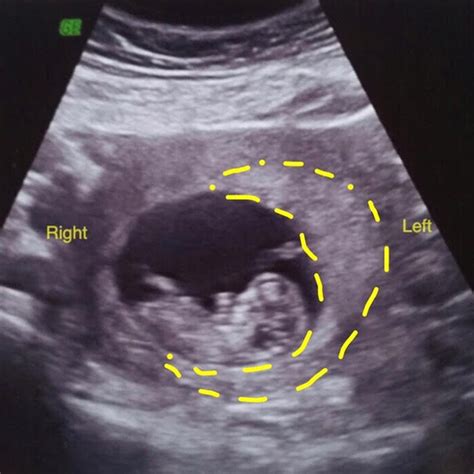

During Ultrasound Week 9 Pregnancy, your baby is undergoing rapid development. The embryo, now measuring about the size of a grape, is developing essential organs and systems. The heart, which has been beating since around week 6, is now more visible on the ultrasound. The neural tube, which will eventually form the brain, spinal cord, and nervous system, is closing. Additionally, the tail, which is a normal part of early development, is beginning to disappear.

• Visualizing the Embryo: At this stage, the embryo is more visible, and you might be able to see the heartbeat and some basic structures.

• Measuring Growth: The technician will measure the crown-rump length (CRL), which is the length from the top of the head to the bottom of the buttocks. This measurement helps determine the gestational age and ensure the baby is growing at a healthy rate.